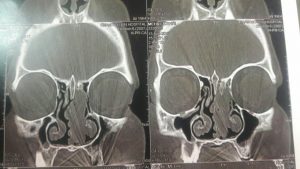

2. سی تی اسکن

تشخیص به وسیله این روش تصویربرداری دقیق تر از سایر روشها می باشد زیرا میزان درگیری استخوان از این طریق نشان می دهد. همچنین برای تشخیص تومور در اطراف مغز از این روش استفاده می شود.

این عکس ها متعلق به خانمی ۵۲ ساله با سابقه گرفتگی بینی از چند سال قبل و نیز سابقه جراحی پولیپ در ۱۰ سال گذشته می باشد در بررسی بالینی نکته دیگری جز توده ای به ظاهر پولیپ مانند در بینی نبود. محل کلی تومور با خط مشکی مشخص شده است

که در تصویر برداری با سی تی اسکن بینی و سینوس نمای موجود شک به این نوع پاپیلوم را برمی انگیخت که طی عمل جراحی اندوسکوپیک و کمک مداوم سر جراحی از همکاران پاتولوژیست وجود این توده ثابت گردیید. و متاسفانه محل پیدایش و منشا اولیه آن در قاعده جمجمه و در محل نازک ترین قسمت استخوان بین بینی و سینوس ها و مغز به طور عملی محرز گردید و این نایحه به طور کامل با کمک ابزارهای خاص تراشیده شده و عمل با اطمینان از برداشت کامل بدون آسیب و صدمه به عناصر حیاتی نظیر مز خاتمه پیدا کرد.